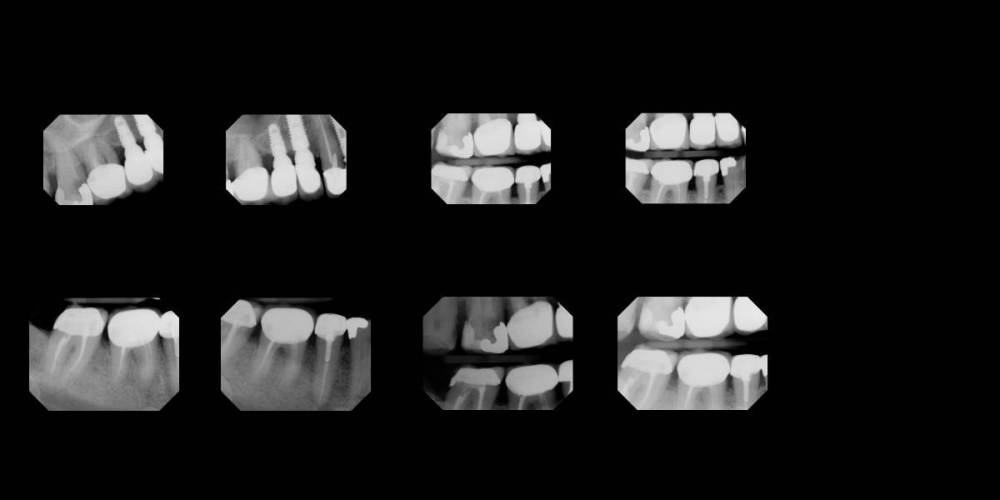

adent Опубликовано 13 января, 2023 Поделиться Опубликовано 13 января, 2023 Здравствуйте! Пожалуйста выскажите ваше мнение по моим вопросам о зубах #1, #2, #30. Боль больше месяца справа внизу и справа в верхнем ряду. Снимки прилагаются. 1.Какова диагностика по этим зубам? 2. Каков может быть план лечения? Два стоматолога дают разные диагнозы и разные методы лечения. Спасибо! P.S Видны ли все 8 снимков? Ссылка на комментарий

IvanK Опубликовано 14 января, 2023 Поделиться Опубликовано 14 января, 2023 Здравствуйте, для проведения диагностических манипуляций нужно минимум ОПТГ (панорамный снимок). На данных прицельных снимках мы видим кусочки пазла То, что бросилось в глаза при беглом осмотре Ссылка на комментарий